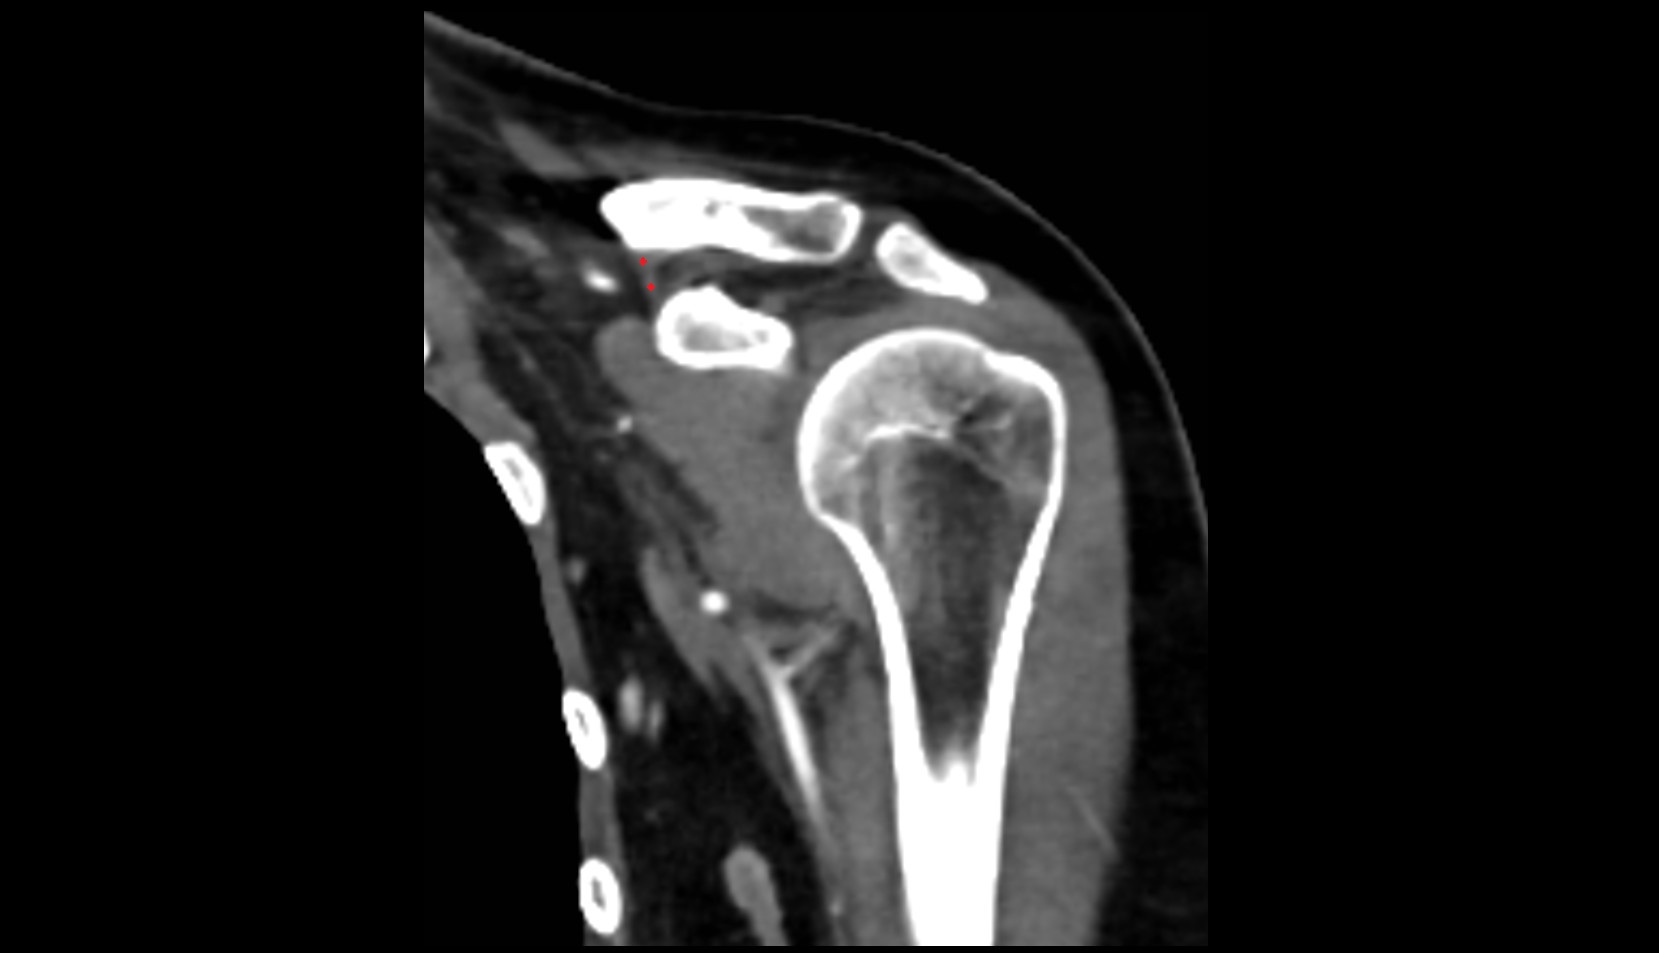

- Glenoid fossa

- Glenoid process of scapula

- Spine of scapula

- Acromion process of scapula

- Coracoid process of scapula

- Scapular body

- Humerus

- Head of humerus

- Shoulder joint (glenohumeral joint)